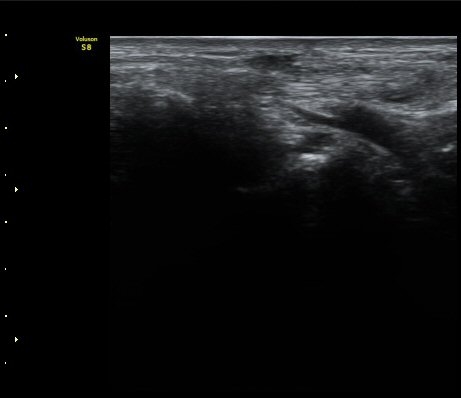

[ÆÈ²ÞÄ¡] ¿»ó ÈÄ ¹ß»ýÇÑ ¿ä°ñ½Å°æ ¸»´Ü °¨°¢½Å°æ ºÐÁö º´Áõ